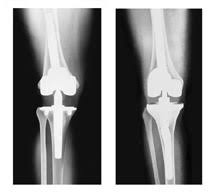

The company ORTHOPEDIC NIKIFOROV was founded in 1998 by the candidate of medical sciences. doctor of orthopedic-traumatologist of the highest category Nikiforov IA Owing to high professionalism and results of work, ORTONIC has gained well-deserved reputation and reputation among colleagues and population of Dnepropetrovsk region and CIS countries (Russia, Moldova, Armenia, etc.). The principle of the enterprise is NO IMPOSSIBLE, it is based on knowledge, experience and active implementation of modern technologies in orthopedics and traumatology. Conservative methods of treatment include individual selection of medicines, therapeutic blockades, manual therapy, massage, physiotherapy (vibration table, magnetotherapy, bioptron, electromyostimulation, etc.), rehabilitation with the suggestion of the necessary concomitant devices and means for the fastest recovery (corsets, bandages, various joint fixators, crutches, walking sticks, etc.). Various minor invasive interventions (chymonucleolysis, vertebroplasty, kyphoplasty, percutaneous nucleoplasty using cold plasma) that are performed on an outpatient basis are successfully used to treat problems associated with spine pathology. The latest modern treatment methods introduced in our company are endoscopic operations using the TYSSES technique of Joimax (Germany) with intervertebral hernias, stenosis and other pathologies of the spine, which allow to avoid complications occurring during open operations and the accompanying general anesthesia. We have many years of successful experience in traditional and modern minimally invasive endoprosthetics of large and small joints, which remains the main direction of our activity. Our company is the exclusive representative of the German company IO International Orthopaedics Holding GmbH, which based on the already known prostheses, its ideas and technological capabilities, has developed and implemented a new concept in hip replacement - an artificial joint prosthesis (ICON). We assist interested colleagues in training the operative technique for installing an artificial joint prosthesis - ICON, both in the workplace and in Germany. For 20 years we have been successfully cooperating with Sanitatshaus Gerd Klinz ortho team, an enterprise that for 20 years has been one of the leading places in Germany for the production of functional prostheses of the upper and lower limbs, as well as cosmetic prostheses of limbs and other body parts (nose, ears, eyeballs, fingers). We have an atmosphere of friendliness and human participation. Politeness, benevolence, the desire to understand and help is the basis of our attitude towards patients. We are always glad to see you and will do our best to make you feel great! We are waiting for you at: Ukraine, Dnepr, Gagarin Ave., 13 (under reconstruction) on all questions to address: tel .: +38 (050) 488-88-92 E-mail: orthonik.ukr@gmail.com Germany, Spine Nano Klinik, Zeppelinstr. 21, Potsdam Tel. +4901801121919 E-mail: kmw.nikiforov@hotmail.de